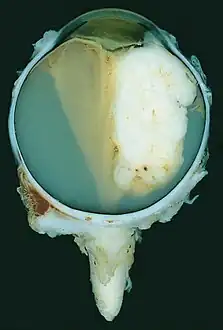

| A pathology specimen of a retinoblastoma tumor from an enucleated eye of a 3-year-old female | |

Morphology

Gross and microscopic appearances of retinoblastoma are identical in both hereditary and sporadic types. Macroscopically, viable tumor cells are found near blood vessels, while zones of necrosis are found in relatively avascular areas. Microscopically, both undifferentiated and differentiated elements may be present. Undifferentiated elements appear as collections of small, round cells with hyperchromatic nuclei; differentiated elements include Flexner-Wintersteiner rosettes, Homer Wright rosettes,[31] and fleurettes from photoreceptor differentiation.[32]

Large exophytic white tumor with foci of calcification producing total exudative retinal detachment